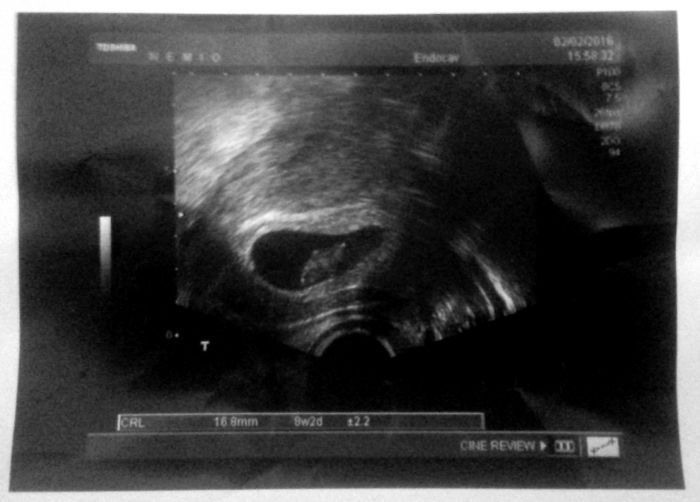

Tak tady davam jeden obrazek - manzel se smal a rika mi: Co to tam mas v sobe za "houbu"? Segre to zase pripada jako drahokam, ja vidim kosodelnik :D Ale na zivo to bylo lepsi, protoze se mimco hybalo, tak to menilo i tvar. Na obrazku to pak vypada "strasidelne" :D

[850709] Ewčo to je krásný a taky vidím kosodelník :-)

Mispule tak snad je to uhnizdovani ;-) Ewco tez vidim kosodelnik, drobet zavidim ale strasne moooc preju..